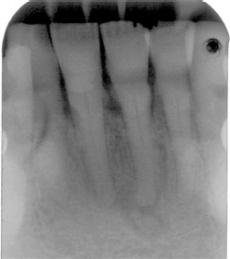

Your patient today is Mei-Yin, a 55-year-old Asian female who is being seen for a routine prophylaxis. She needs radiographs, and, after evaluating the images, you are concerned about the radiolucent apical area on No. 24. She is currently taking medication for acid reflux and occasionally uses ibuprofen for joint discomfort. She also takes Zyrtec (10mg. qd) for seasonal allergies.

Mei-Yin states that she does not have any pain related to her teeth. She has some periodontal bone loss and calculus, but is otherwise very healthy. Some mobility of the mandibular teeth is noted, and no lymphadenopathy is evident. She does not remember any previous trauma to this area of her mouth. You explain to her that the concern is the area in the apical region of her mandibular tooth and you show her the area of concern on the radiograph. Palpation of the area is crucial, as well as a thorough oral exam and cancer screening.

With cases of cemento-osseous dysplasia, confusion can occur when the clinician believes that the tooth may need a root canal or extraction based on the radiographic appearance. Three variations may occur in the clinical appearance (Komabayashi and Zhu, 2011) such as:

- Early stage (radiolucency without radiopacity inclusion)

- Mixed stage (radiolucency with radiopacity inclusion)

- Mature stage (radiopacity). This stage is more radiopaque, but, as you can imagine, the degree of both radiolucent and radiopaque appearances may vary greatly.

Generally, there is suspicion of a diseased state whether a mixed radiolucent area or opaque lesion is present. A diagnostic investigation would include testing for percussion, palpation, cold testing (ice), and an electric pulp test. Periapical cemento-ossifying dysplasia would present with a vital pulp.

Clinical appearances, health implications, ethnicity, and age would be factors that the practitioner would take into consideration in a diagnosis. The key factor involving the periapical cemento-osseous dysplasia is pulp testing. The tooth will test vital.A periapical inflammatory lesion may be diagnosed if pulp testing is not performed and a diagnostic workup is not performed as part of the treatment plan. The patient may be referred for endodontic treatment (root canal) when it is not necessary.

Often, the periapical cemento-osseous dysplasia can be followed when the patient is seen periodically over a long period of time. The second image presented here occurred over a 23-year period with observation (see Figure 2).